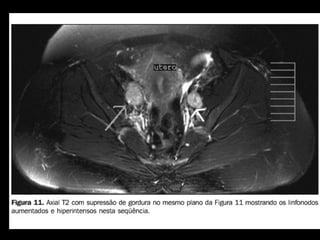

LINFONODOS - RM

• FIGO NÃO CONSIDERA

• Tamanho e forma são

importantes para predizer

neoplasia:

– Esféricos e > 1 cm =

anormais

– Necrose central = VPP

quase 100% para MT